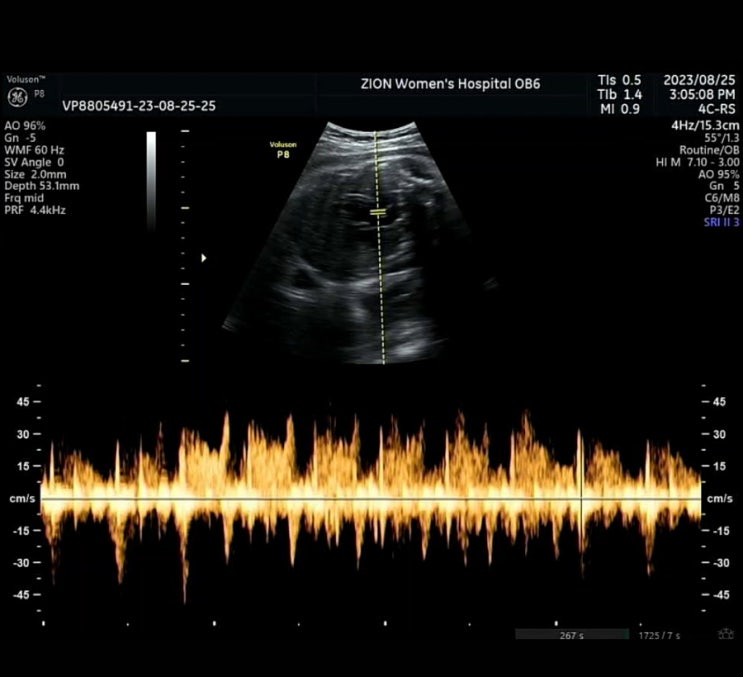

[ 임신기록 ] 임신38주 제왕 날짜 잡았어요

23.08.23 (임신38주) 이제 얼마 안남았다라고 생각하며 병원가기전, 타이니모빌 조립도 하고 출발.. 시온병...